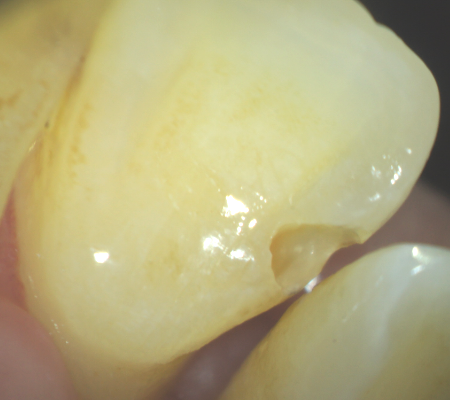

今まで、歯科治療において手探りともいえる外科の歯科治療だと感じていました。それは、口の中とは見えそうでよく見えないところが多く、照明をあてたとしても暗くて、また狭く、陰に隠れてしまう部分が多いです。

実際に診に見えないところを、レントゲンを参考に想像しながら、経験と勘で治療していたといっても過言ではありません。 しかしマイクロスコープ(顕微鏡)を使うと確実に肉眼で見ながら治療できるようになり、とても精度の高い、成功率の高い歯科治療ができるようになります。

マイクロスコープ(顕微鏡)治療は特に、根の治療(根管治療)や歯根端切除、修復・充填、かぶせ(インレー・クラウン・ブリッジ)、抜歯等において私には欠かせない右腕となっています。